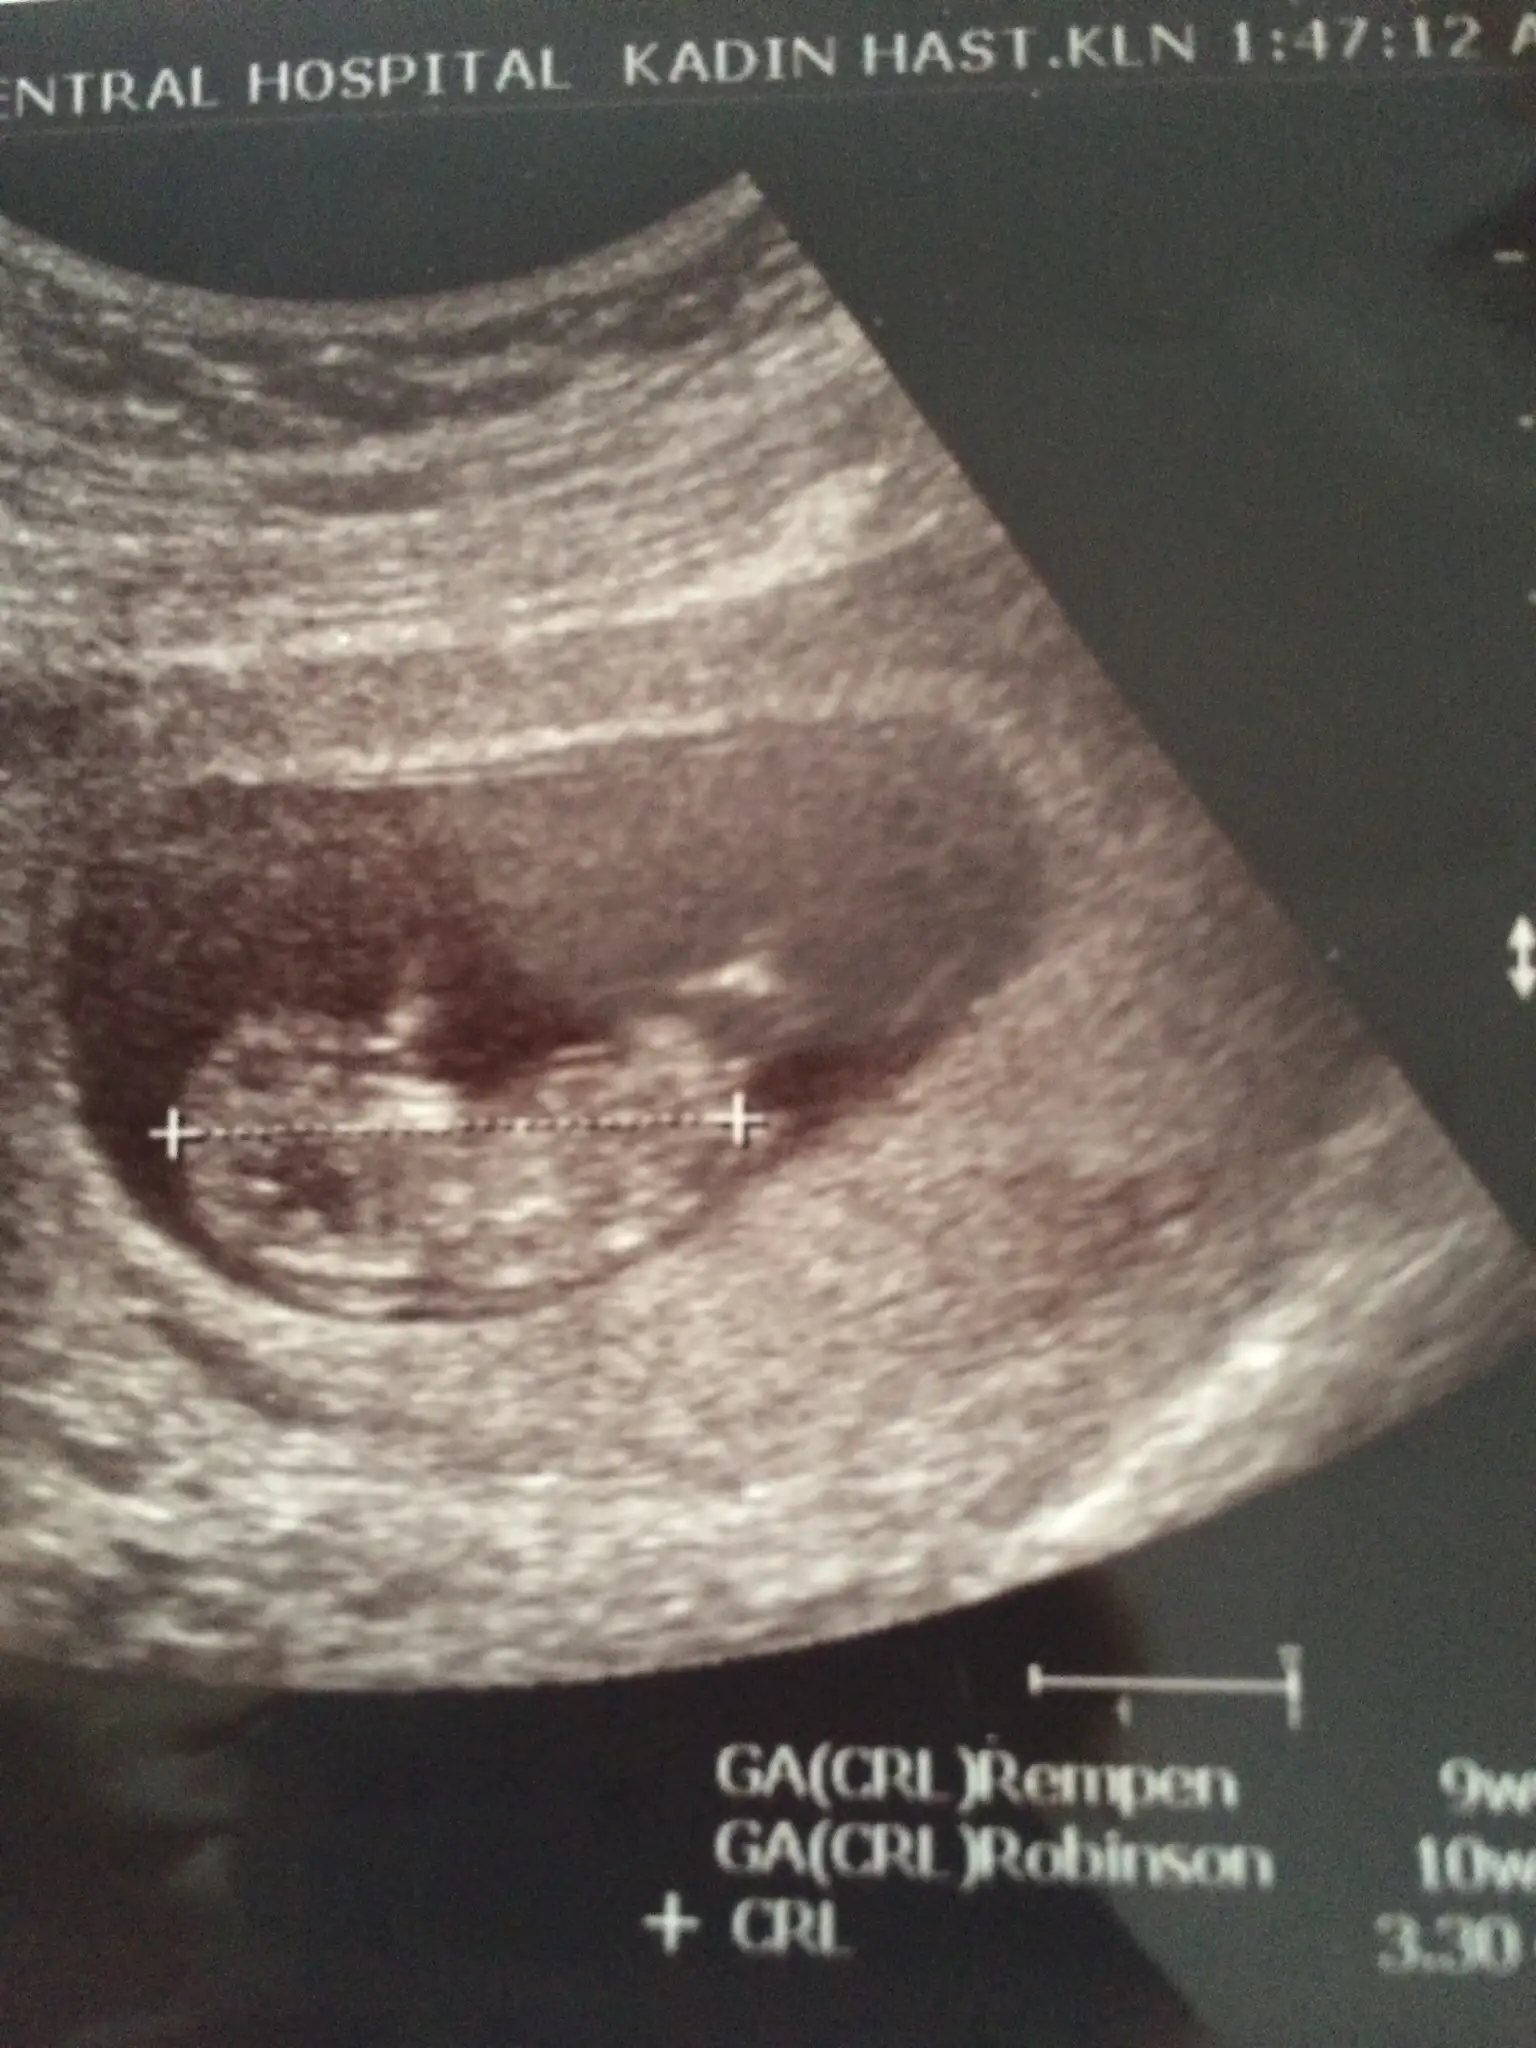

image.webp Buda bizim 10 haftalık usgmiz var mı tahminde bulunabilecek